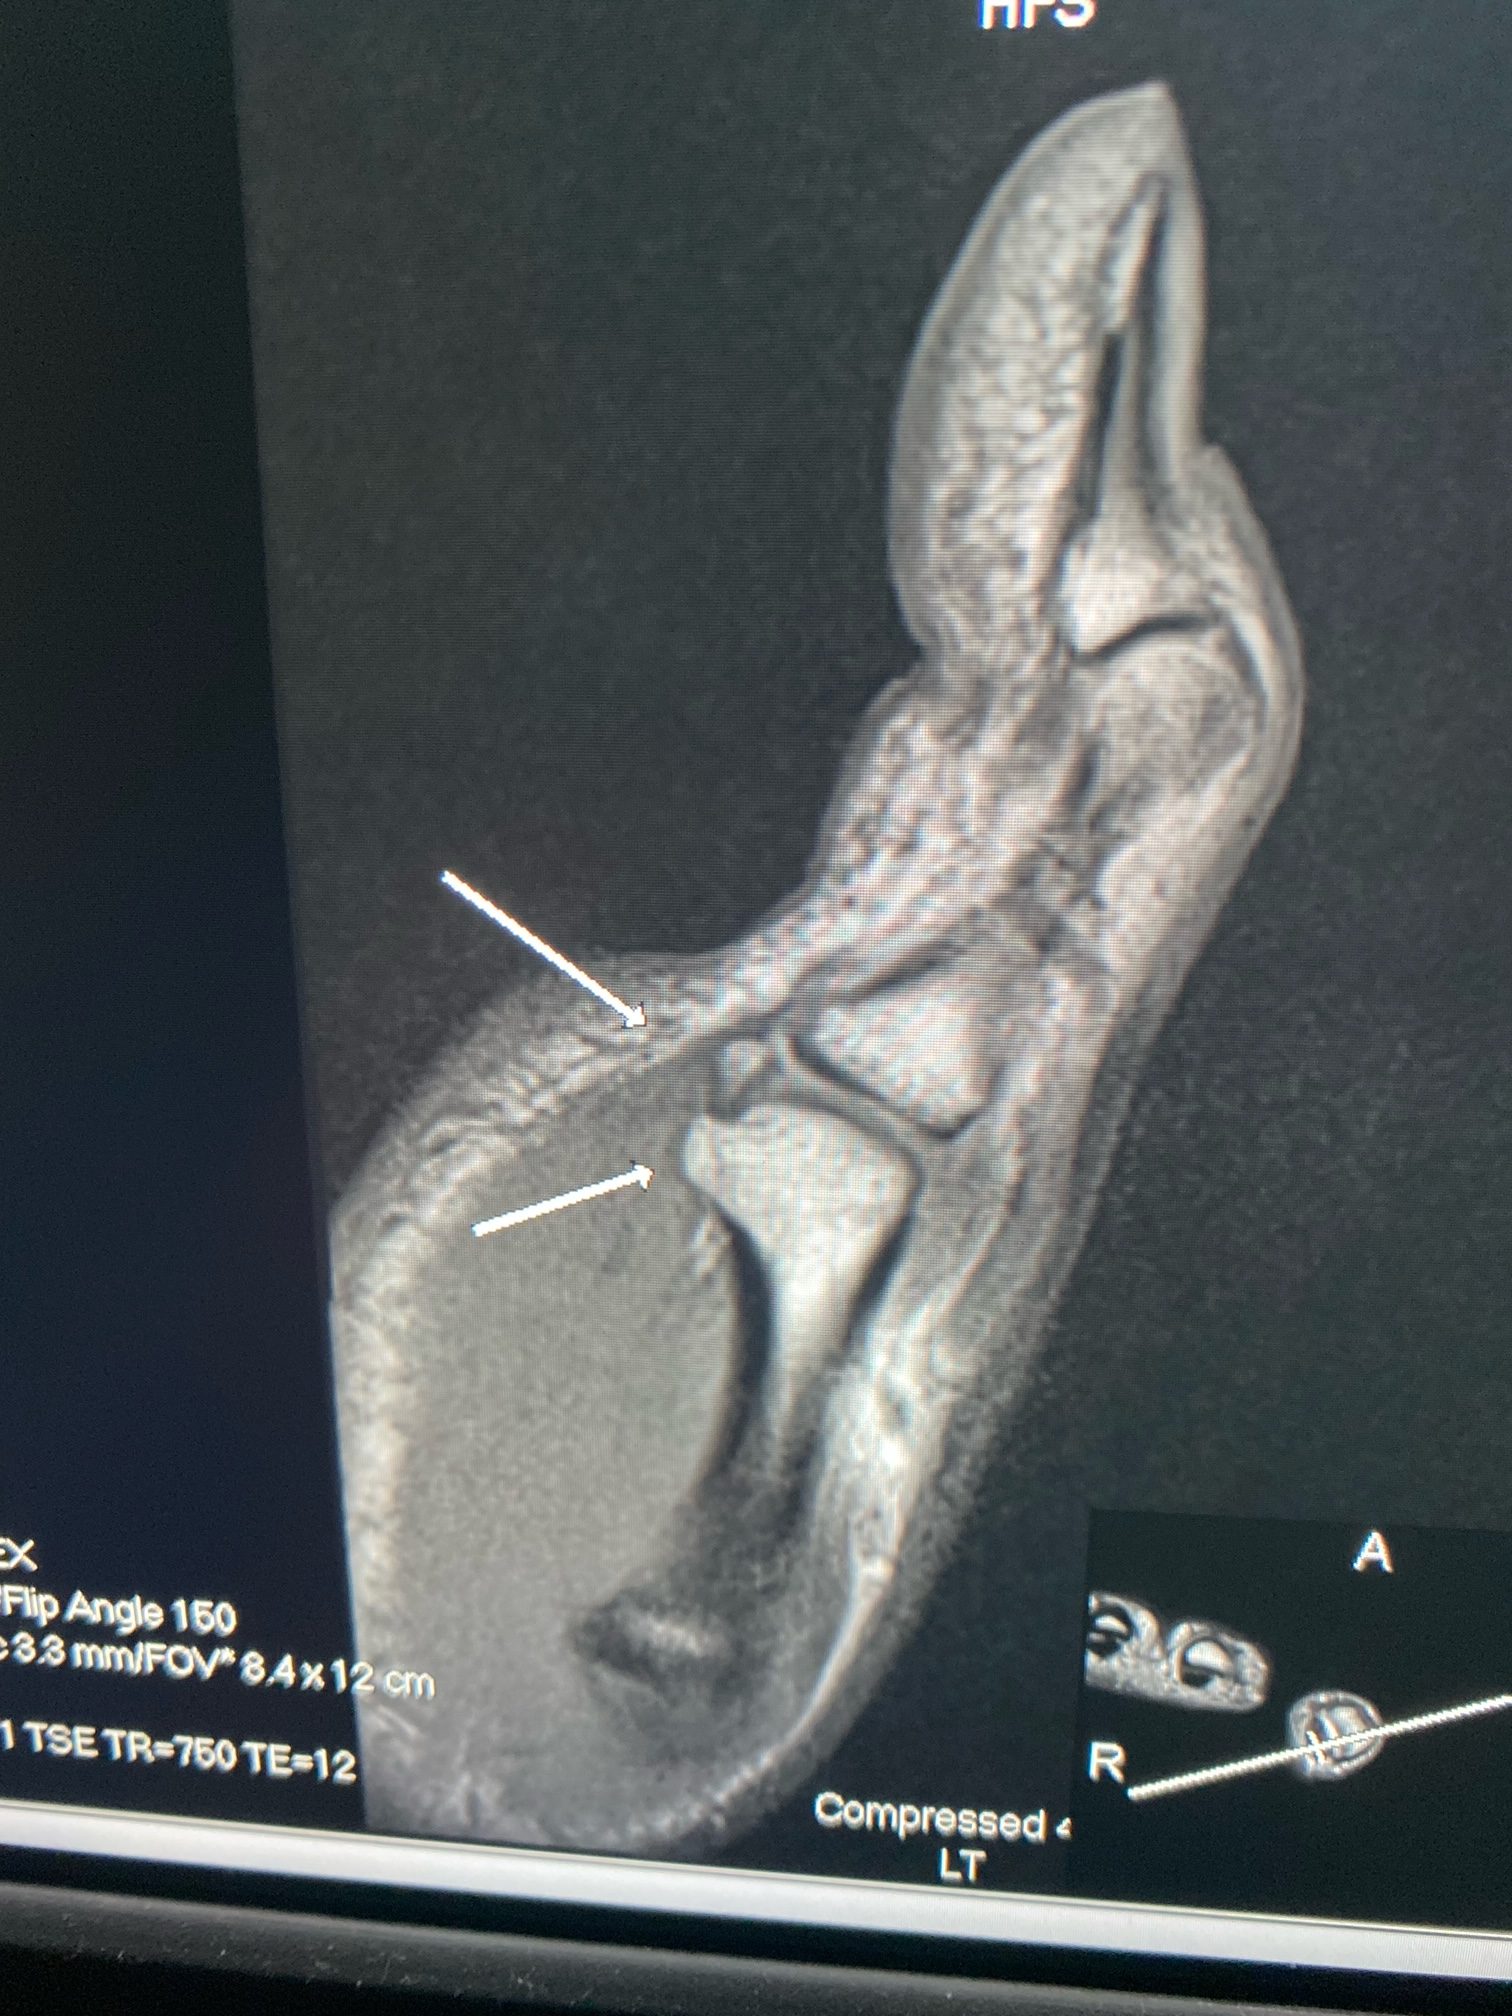

From ocadmsk.com

Locked sesamoid at thumb mcp joint OCAD What Causes Locked Thumb Joint  Trigger finger is a condition that affects the tendons and pulleys of the fingers or thumbs, causing pain, swelling, stiffness and locking. Learn about the possible causes, symptoms. Trigger finger is a condition that affects the tendons of the fingers and thumb, causing them to catch or lock when bending or straightening. Learn about the possible causes, diagnosis and. It. What Causes Locked Thumb Joint.